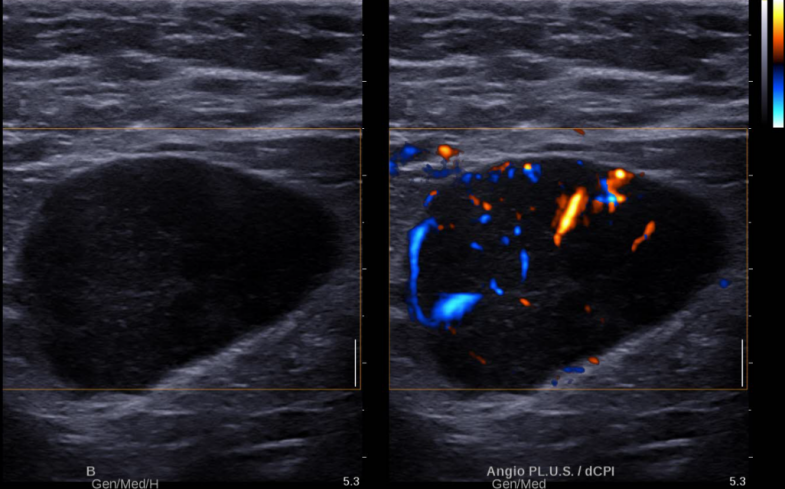

图 1 腋窝低回声结节微血管成像图(线阵探头)

右侧腋窝腋动脉深方可见一个低回声结节,大小约 36×25mm ,呈椭圆形,边界清晰,形态规则,内部回声分布不均匀,未见明显淋巴门结构。

彩色多普勒

右乳低回声结节内未见明显血流信号。右侧腋窝低回声结节微血管成像内可见较丰富条状周围型血流信号,未见明显门性血流信号。

右乳低回声结节, BI-RADS 3 类,建议定期随访,右侧腋窝低回声结节,神经鞘瘤可能,建议粗针穿刺活检(图 1-3 )。